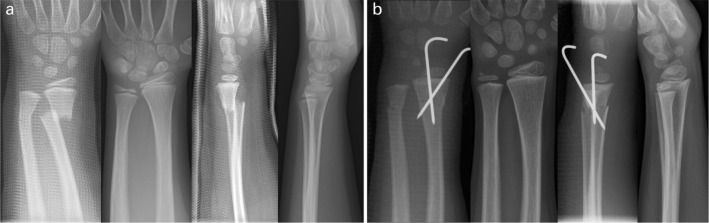

Fig 1.

a) Distal forearm fracture in a five-year-old girl (Table 1, case 3), which was immobilized with synthetic splints (above elbow dorsal and a below elbow volar) applied in finger trap traction leaving the radius in bayonet position. Immobilization was discontinued at four weeks. Complete radiographic remodelling is evident 43 months later; b) a similar distal forearm fracture in another five-year-old boy (Table 1, case 14), which was treated by reduction and pin fixation under general anaesthesia. Synthetic splints and both pins were removed four weeks after surgery. Radiographic result 43 months later.

In all, 11 of the 13 patients whose fractures were not reduced, but were immobilized in the bayonet position, came to a clinical examination and had radiographs of their injured forearms taken. One girl denied attending the clinical examination, but agreed to be interviewed by phone and have her radiographs taken (Table 1, case 5). One five-year old boy, who claimed to have no pain and normal function four years after the fracture, was excluded from the analysis because he refused to attend both the clinical and the radiographic follow-up examinations. We then chose 12 age-matched children that had their completely displaced distal metaphyseal radius fractures reduced and pin fixed, who all agreed to be called-back for research purposes (Fig. 1b). In the 24-patient study population 22 children had different types of associated ulna fractures (greenstick: nine, complete in overriding position: seven, torus: five, physeal: one) with an uneven distribution between the treatment groups (Table 1).